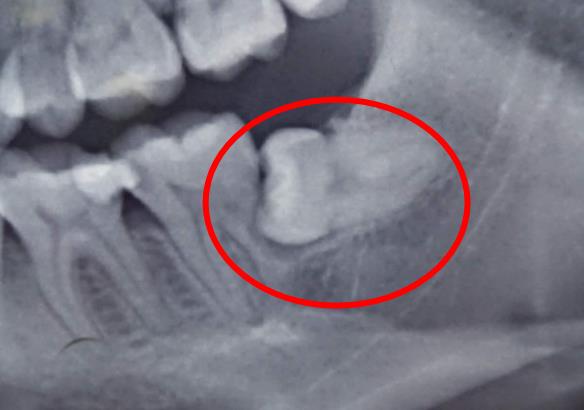

阻生智齒造成鄰牙齲壞

不過,部分牙齒阻生,需要及時拔除,比如反複發炎,造成智齒冠周炎發作,疼痛嚴(yan) 重;或者說智齒引起鄰牙第二磨牙齲壞受損;智齒對全口牙齒造成擁擠等情況,是建議盡早到醫院檢查確診後,及時拔牙的。

阻生智齒還可能會(hui) 造成口腔清潔不到位,食物殘渣滯留,滋生細菌出現蛀牙等後果。

3、頂著鄰牙,齲壞鄰牙,這也可能是很長一段時間內(nei) 會(hui) 出現的問題。